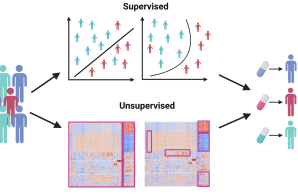

Central Project 2: Bioinformatic data integration and multi-omic pathway analysis

CP2 will offer bioinformatics support for every stage of the computational analysis of clinical and omics data generated in the ProBone project, this includes sample collection, experimental design, harmonized data analysis, and hypothesis generation and validation. CP2 will concentrate on identifying patient subtypes in early-onset low BMD disorders and the disease mechanisms that differentiate these subtypes.